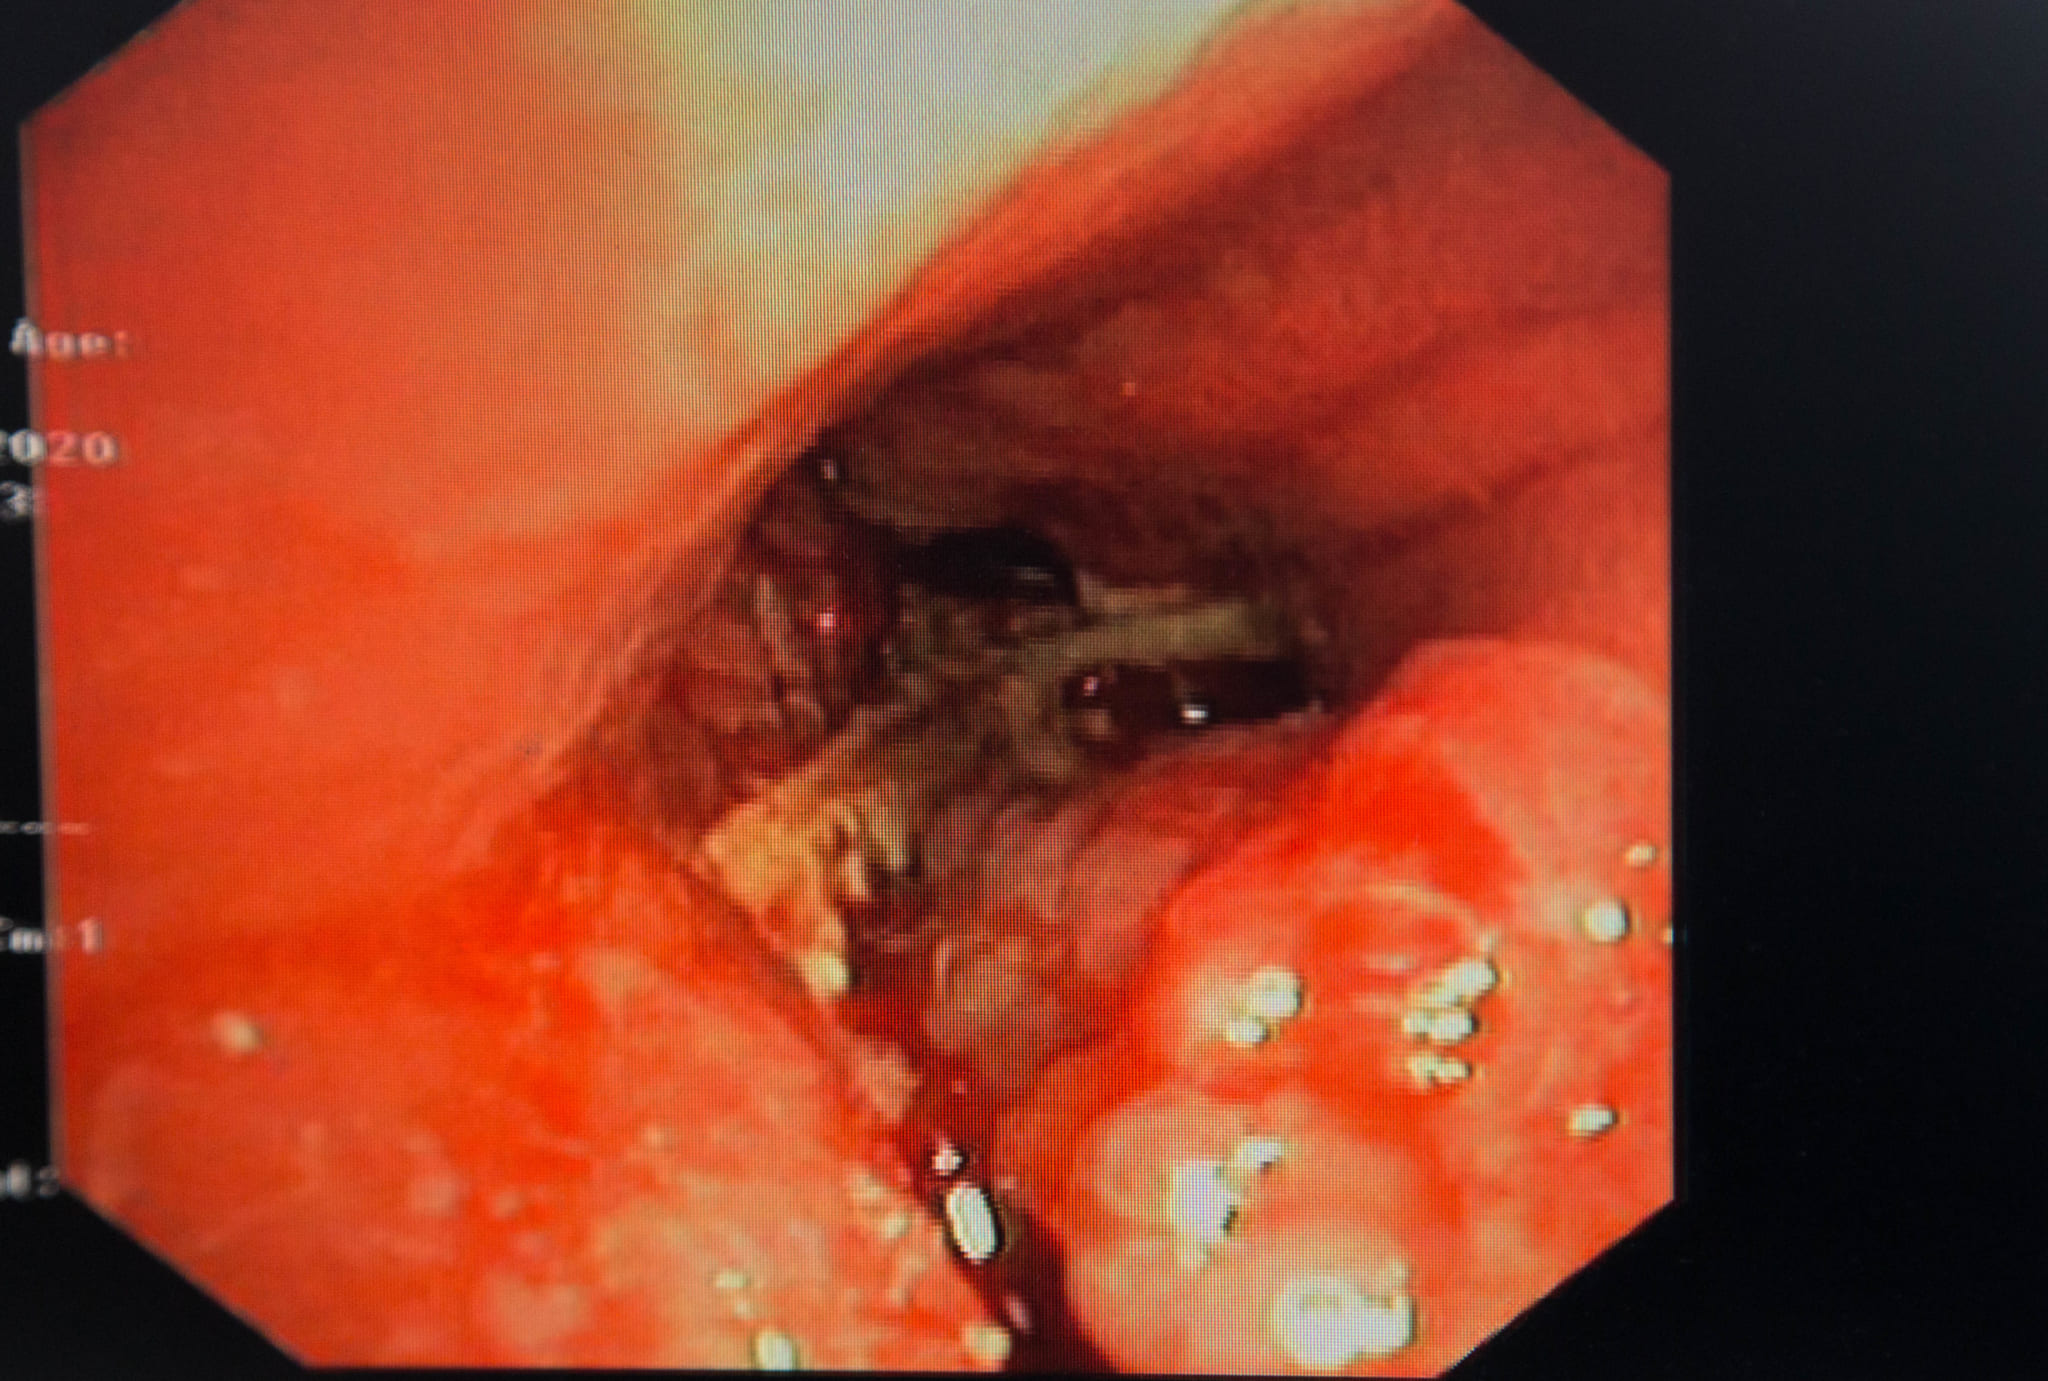

Bệnh nhân được BSCKII Lê Thị Trâm, Trưởng Đơn nguyên Chăm sóc toàn diện thăm khám và qua nghe phổi, bác sĩ đã nghe thấy tiếng rít phế quản ở phổi phải người bệnh. Bệnh nhân đã được chỉ định chụp CT, phát hiện nghi tổ chức cản quang nằm trong lòng phế quản thùy dưới phổi phải. Tiến hành nội soi phế quản, phát hiện thấy phế quản trung gian nhiều tổ chức sùi, chảy máu trong lòng phế quản, nhìn thấy dị vật là mảnh xương nằm vắt ngang phế quản thùy dưới phổi và một phần áp sát phế quản trung gian. Có nhiều mủ chảy ra ở phế quản thùy dưới.

Bệnh nhân đã được BSCKII Lê Thị Trâm, Trưởng Đơn nguyên Chăm sóc toàn diện cùng kíp thực hiện tiến hành nội soi phế quản gắp dị vật, cầm máu. Chỉ sau 30 phút, bác sĩ đã gắp thành công dị vật là mảnh mang xương cá, kích thước 2cm ra khỏi phế quản phải cho bệnh nhân. Ngay sau thủ thuật, tình trạng sức khỏe người bệnh ổn định, đỡ ho, không tức ngực và hết khó thở.